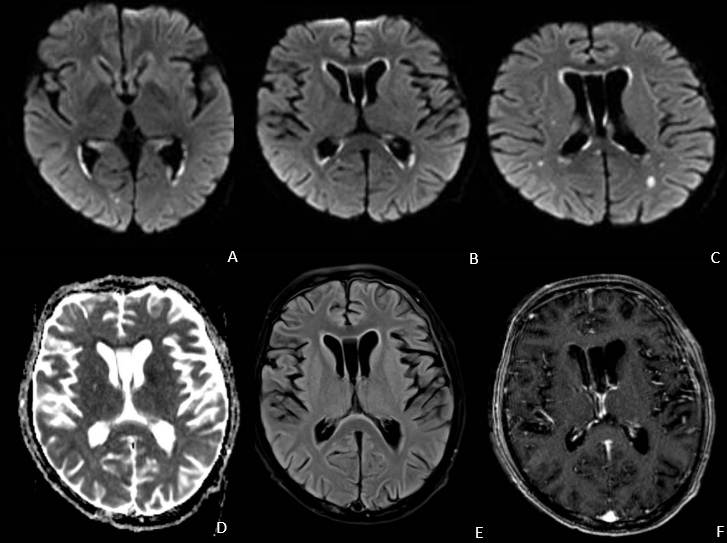

Ventriculitis por citomegalovirus (CMV)

- RM es el método de elección

- El CMV afecta a la sustancia gris y el epéndimo ventricular en mayor grado que a la sustancia blanca, lo que lo distingue de otras encefalitis en pacientes VIH

- El hallazgo más característico es la presencia de una hiperintensidad subependimaria en la secuencia FLAIR con realce tras la administración de contraste intravenoso y restricción a la difusión

- Puede tener un extensión centrífuga desde el sistema ventricular a la sustancia gris o blanca.